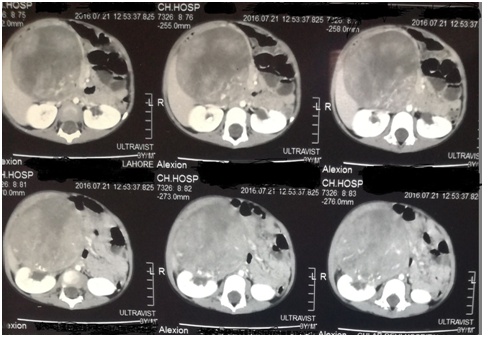

CT scan of the abdomen showed an approximately 20x 10 x 9 cm sized mixed density heterogeneously enhancing mass in the right hemi abdomen. It was compressing and abutting the inferior surface of right lobe of liver pushing it upwards. The mass was also compressing the right kidney and displacing it laterally. There was no abdominal lymphadenopathy. Aorta and IVC appear normal with no vascular encasement [Figure 1Figure 2].

Figure 1 CT scan of the abdomen showed an approximately 20x 10 x 9 cm sized mixed density heterogeneously enhancing mass in the right hemi abdomen.